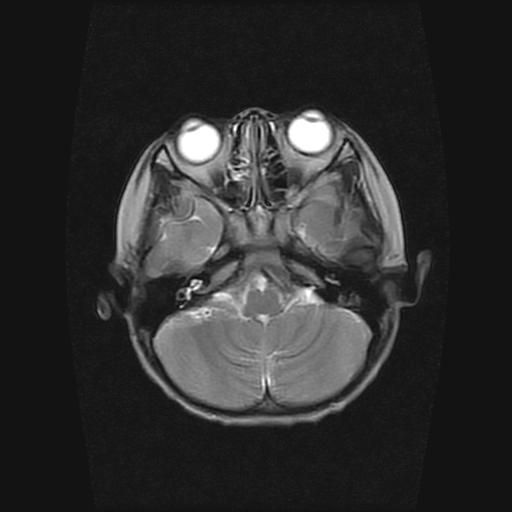

6岁小儿,左侧视神经瘤术后。现左侧视力减退。